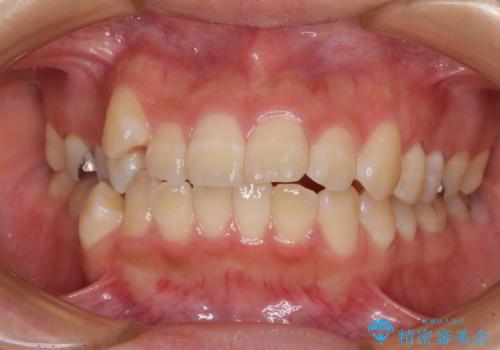

隙間が空いて突出した前歯を治したい ワイヤー装置による抜歯矯正